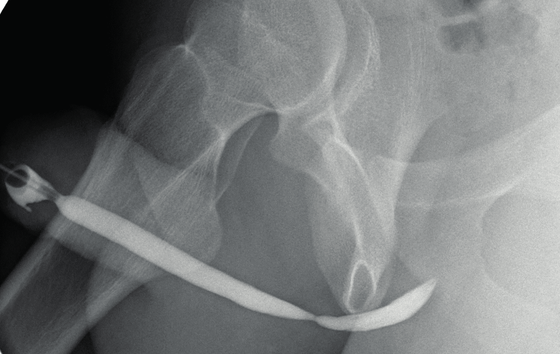

Retrograde Urethrogram

Het doel van dit onderzoek is de plasbuis (urethra) zichtbaar te maken met behulp van röntgenstralen. U krijgt tijdens het onderzoek via een katheter contrastmiddel toegediend. Zonder dit contrastmiddel is de plasbuis niet zichtbaar op de röntgenfoto.

U wordt voor het onderzoek door een laborant uit de wachtkamer gehaald. Als u nog vragen hebt dan kan u deze aan de laborant stellen. Voorafgaand aan het onderzoek vraagt de laborant u naar het toilet te gaan en de blaas goed te legen. Bij de kleedkamer is een toilet. U neemt plaats op de röntgentafel. Vervolgens schuift de radioloog een slangetje in de plasbuis. Aan het slangetje zit een ballonnetje dat wordt opgeblazen. Dit ballonnetje voorkomt dat het slangetje tijdens het onderzoek gaat verschuiven.

Vervolgens spuit de radioloog door dit slangetje een contrastvloeistof tot in de blaas. Zodra de plasbuis goed is gevuld, maakt de radioloog röntgenopnamen. Heeft de radioloog voldoende opnamen gemaakt, dan laat hij het ballonnetje leeglopen en wordt het slangetje verwijderd. Het onderzoek is dan klaar. Het onderzoek duurt in de meeste gevallen ongeveer 30 minuten.

De radioloog beoordeelt de beelden na afloop van het onderzoek. Hij maakt een verslag en stuurt dit naar uw uroloog. Uw uroloog bespreekt met u de definitieve uitslag.